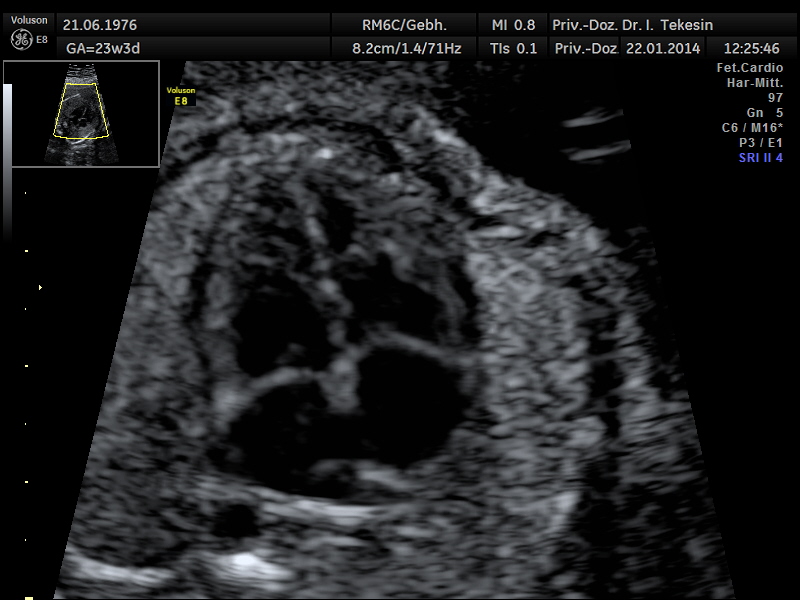

Fetale Echokardiographie

Ein weiterer Bestandteil der weiterführenden Ultraschall-Diagnostik ist die Beurteilung des kindlichen Herzens und der großen Blutgefäße, die fetale Echokardiographie. Dabei untersuchen wir die Lage, Größe und Symmetrie des Herzens, Anatomie der Herzstrukturen, Funktion der Herzklappen, Herzfrequenz und die Lage der großen Gefäße. Mit Hilfe der farbkodierten Doppler-Sonographie des Herzens werden weitere Details untersucht: die Funktion der Herzkammern, Herzscheidewände, Blutflüsse im Herzen und Blutflüsse in den großen Gefäßen.

Das Ziel dieser Ultraschalluntersuchung des fetalen Herzens ist der weitest mögliche Ausschluss von angeborenen Herzfehlern. Die Voraussetzung hierfür sind eine spezielle Ausbildung und Erfahrung des Arztes in Verbindung mit der hohen Qualität des Ultraschallgerätes.

Jährlich werden in Deutschland etwa 7000 Kinder mit strukturellen Herzfehlern lebend geboren. Damit zählen Herzfehlbildungen mit ca. 1:100 zu den häufigsten angeborenen Fehlbildungen überhaupt. Bei etwa der Hälfte der Herzfehlbildungen besteht aufgrund der Schwere der Ausprägung eine Operationsnotwendigkeit. Durch Verbesserung der pränatalen Diagnostik kann die Erkennungsrate fetaler Herzanomalien deutlich erhöht werden, um damit den kleinen Patienten durch unmittelbare fachkompetente Behandlung einen besseren Einstieg in das Leben zu ermöglichen.

Dank der zunehmenden Verbesserung der Geräte und durch die Qualifizierung besonderer Ärzte kann auch ein Großteil der Herzfehlbildungen bereits zwischen 13. und 14. SSW erkannt bzw. ausgeschlossen werden.

Die endgültige Beurteilung des Herzens, seiner Funktion und der Blutflüsse, erfolgt jedoch erst zwischen 19. und 21. SSW und sollte in der Regel mit der 22./23. SSW abgeschlossen sein. Zu einem späteren Zeitpunkt in der Schwangerschaft ist die Diagnostik häufig durch die ungünstige Lage des Kindes sowie durch die schlechte Schalldurchlässigkeit der Rippen beeinträchtigt.

Mit Hilfe der fetalen Echokardiographie lassen sich die meisten der angeborenen Herzfehler (ca. 83 %) erkennen. Es gibt jedoch auch Herzfehler, die in der 20. Schwangerschaftswoche noch nicht (oder schwer) erkennbar sind. Dazu gehören Verengungen an den Herzklappen, deren Folgen erst später sichtbar werden. Auch ein kleines „Loch" in der Trennwand der Herzkammern ist nicht immer feststellbar.

Die meisten angeborenen Herzfehler können heutzutage sehr gut operiert werden. Die Erfolgsrate der Behandlung steigt nachweislich bei vorgeburtlicher Entdeckung. Bei Feststellung bzw. einem Verdacht auf einen fetalen Herzfehler erfolgt eine gezielte Beratung unter Hinzuziehung von Kinderkardiologen. Wir besprechen mit Ihnen, wo und unter welchen Bedingungen die Geburt stattfinden sollte und wie das Vorgehen nach der Geburt aussieht.

Normaler Vierkammer-­‐Blick

Normaler Vierkammer–Blick mit Farbe

Normaler Vierkammer-Blick

Normaler Vierkammer-Blick mit Farbe

Normales Herz in der 24. Woche

Normales Herz in der 22. Woche